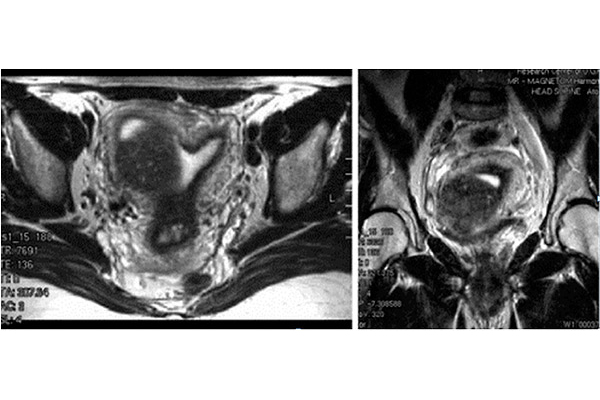

- МРТ органов малого таза. Дает наиболее полную информацию о состоянии матки и наличии аденомиоза.

На фото ниже продемонстрировано МРТ узлового аденомиоза с подслизистым расположением новообразования.